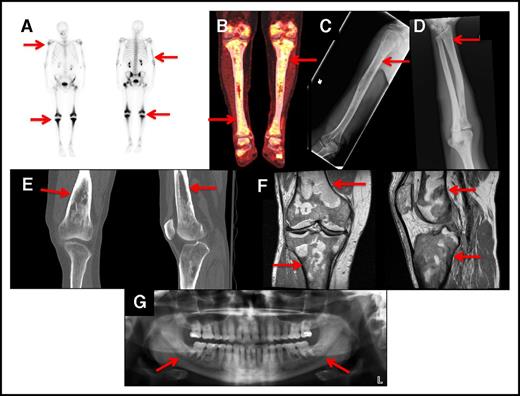

Bone disease

Bone lesions in ECD are described as osteosclerosis or polyostotic sclerosis as evident on scintigraphic studies of long bones.7,8 Bone involvement was present in 95% of cases and involved the appendicular skeleton and occasionally the axial skeleton. Technetium-99 bone scans (Figure 1A) and FDG PET-CT scans (Figure 1B) revealed increased uptake in affected areas. Long bone osteosclerosis was detected on plain radiographs (Figure 1C-D), CT (Figure 1E), and MRI (Figure 1F). Panoramic imaging showed bilateral midroot radiolucencies in the maxilla and mandible (Figure 1G) in 47% of cases (n = 51). For long bones, bilateral involvement was seen in the femur in 88% of patients, tibia in 88%, humeri in 42%, and radii in 42%. In addition, the skull, vertebrae, mandible, pelvis, and ribs occasionally contained lesions, and MRIs of the head showed thickening of the facial bones and maxillary sinuses in 50% of cases. Technetium-99 bone scan was the imaging modality with the highest sensitivity in detecting bone disease when compared with plain film radiographs. Plain radiographs detected osteosclerosis in the radii in 42% of patients (26 out of 60) and in the femur and tibia in 60% (36 out of 60) and 65% (39 out of 60), respectively. In comparison, T-99 bone scans showed increased radiotracer uptake in the radii in 47% of the cases (28 out of 60) and in the femur and tibia in 88% (53 out of 60). There was no evidence of bone disease in 5% of the cases. In our series, 82% of patients had received therapy prior to our evaluations. Approximately half of the affected individuals described deep, dull bone pain, especially in the knees.

Bone lesions in ECD. The red arrows show: (A) Whole-body bone scan with technetium-99 showing avid uptake in the knees and left hip of an ECD patient. Less intense uptake occurs bilaterally in the humeri and distal tibias. (B) FDG PET-CT scan showing increased FDG uptake in the knees and proximal and distal tibias. (C) Bone radiograph showing cortical osteosclerosis in the right humeri. (D) Bone radiograph showing cortical osteosclerosis in the distal right radius. (E) CT scan of the right knee of an ECD patient showing cortical osteosclerosis and mottled appearance of the bone. (F) MRI scan of the right knee of an ECD patient showing serpiginous areas of T1 signal hypointensity, indicative of osteosclerosis. (G) Panoramic radiograph showing bilateral osteosclerosis of the mandible and maxillary sinus disease.